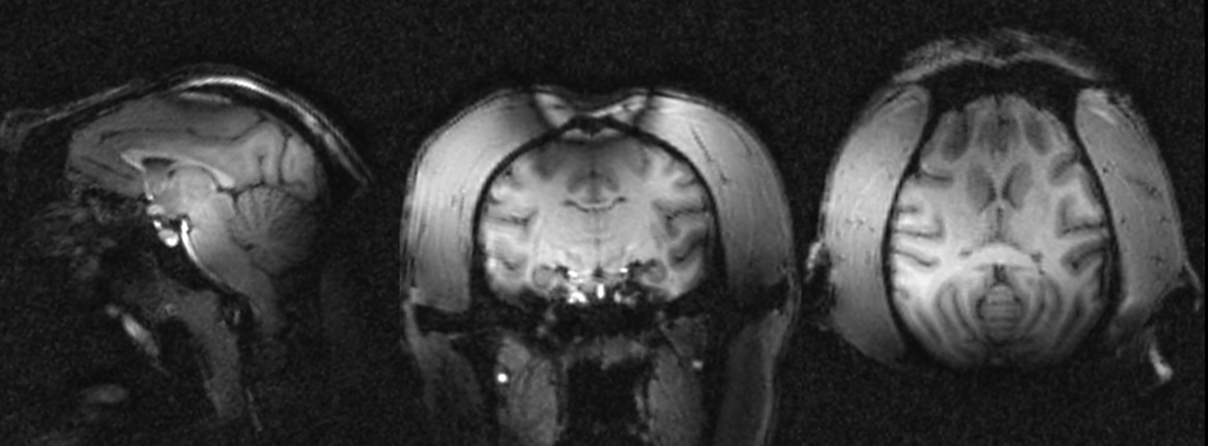

Figure 2 illustrates the quality of the 300-µm and 500-µm isotropic raw GRE and Maximum Intensity Projection images (MIP) of the same images. Figure 3 displays 800-µm T1-weighted MPRAGE images

In vivo MRI data acquired in one macaca rhesus at 11.7 T with 3D MPRAGE sequences in pCP mode. The images were reconstructed from left to right respectively in sagittal, coronal and transversal planes with 3D MPR out of 800um isotropic acquisitions. The images reveals classic T1 weighted contrast but also strong B0 artefact on the top of the head because of poor shimming and signal losses mainly in the back of the head probably due to the inversion pulse operating out of the adiabaticity regime.